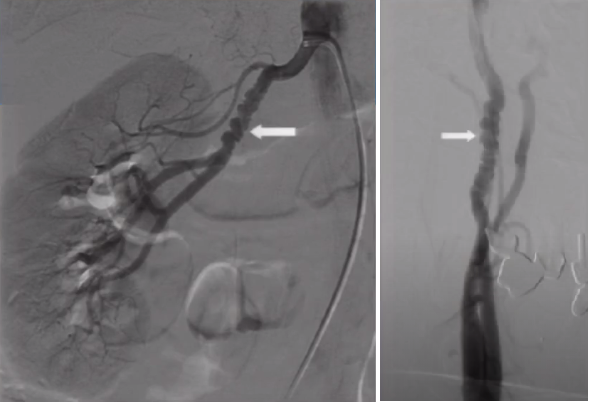

3. 颈动脉蹼(Carotid artery web)

➤ 动脉腔内隔膜状突出物(有时班瘤样扩张),多出现在颈动脉球部,为非典型的内膜下棘状细胞纤维增生物,不伴内皮的增生,无炎性细胞浸润,无脂质浸润;

➤ 多发生在颈动脉(颈动脉球附近),也可见于椎动脉;

➤ 引起血管狭窄;在蹼的远心面形成血流的滞留区,从而产生血栓;

➤ CTA上可见血管腔内充盈缺损,DSA上尚可见到造影剂滞留。

图3 颈动脉蹼

➤ 颈动脉体瘤合并FMD

图9 一位54岁女性,因为颈动脉体瘤而行术前DSA检查,显示并存的纤维肌发育不良